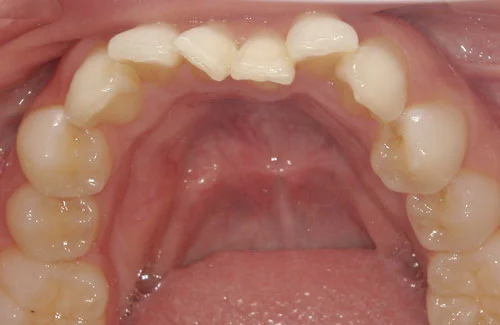

- 症例1

治療期間 約3カ月

プラン アーリープラン(8枚コース)

治療費 33万円(税込)